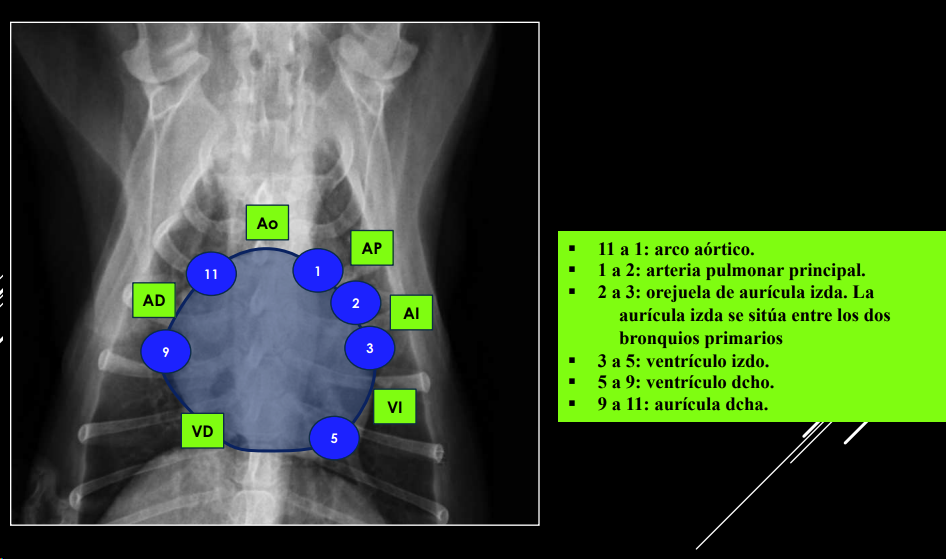

POSICIÓN DE CÁMARAS Y GRANDES VASOS (“analogía del reloj”)

Se puede comparar la silueta cardíaca con la esfera de un reloj <analogía del reloj=,utilizando los intervalos horarios para la localización de las cámaras cardíacas y de los grandes vasos.

Proyección DV:

- 11–1: arco aórtico.

- 1–2: arteria pulmonar.

- 2–3: orejuela AI.

- 3–5: ventrículo izdo.

- 5–9: ventrículo dcho.

- 9–11: aurícula dcha.

Proyección LL:

- Craneodorsal: aorta y atrio derecho.

- Craneoventral: ventrículo derecho.

- Caudodorsal: atrio izquierdo.

- Caudoventral: ventrículo izquierdo.